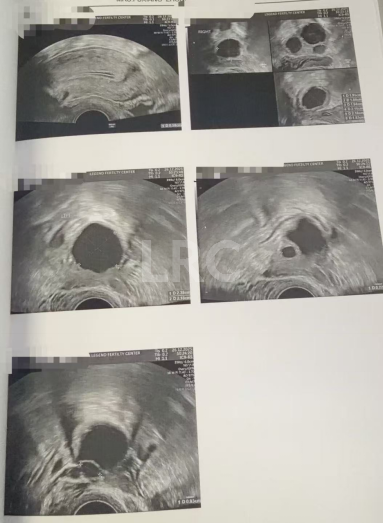

月经第二天 促排第一天

阴超检查:基础卵泡 4 颗

- 右侧卵泡 3 颗 (9,7,7,4mm)

- 左侧卵泡 1 颗 (9mm)

促排第五天

阴超检查(只数能用卵子):

- 右侧卵泡 3 颗 (14,12,11mm)

- 左侧卵泡 1 颗 (14mm)

促排第八天

阴超检查:

- 右侧卵泡 3 颗 (18,16,14mm)

- 左侧卵泡 1 颗 (18mm)

促排第九天

- 右侧卵泡 3 颗 (20,20,18mm)

- 左侧卵泡 2 颗 (23mm)

子宫内膜厚度:5..8mm

▲ Z女士的取卵报告

精细化全程监测,筑牢卵子成熟保障:从月经第二天的基础数据建档,到促排第5、8、9天的动态跟踪,LRC医疗团队通过阴超实时监测卵泡大小、数量变化,同步把控促黄体生成素、雌二醇等关键激素水平,甚至精准捕捉到左侧新增 1 颗成熟卵泡的发育信号。这种数据驱动、实时调整的监测模式,既确保了卵泡均匀发育,又为取卵时机的精准判断提供科学依据,是全卵子成熟的重要保障。